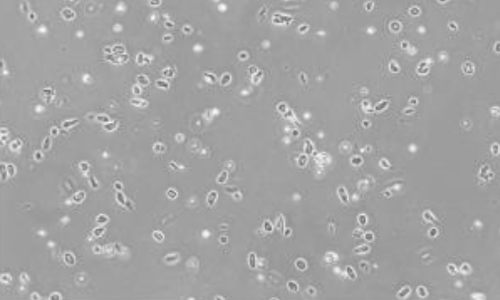

▲人肝脏 FFPE 样本 |